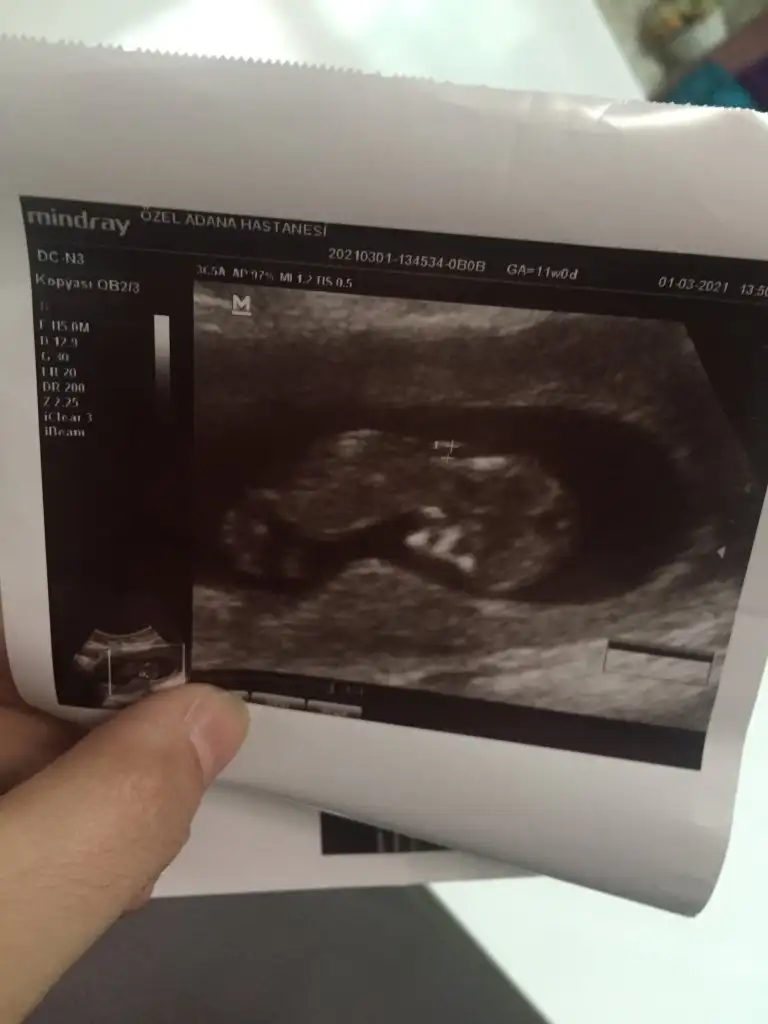

Herkese merhaba.bugün detaylı bakıldık ultrasonda hocamız şükür herşey yolunda dedi.yaşımdan dolayı korkuyordum ama içim rahatladı.bir genetik test önerdi fiyat fazla ama yaptırıyorum Amerika’ya gidecek kan örneği.sonuç inşallah iyi çıkar dua istiyorum hepinizden🙏Cinsiyet tahmin edebilecek olan var mı🙏

Cinsiyet tahmin edebilecek var mı?

Eklentiler

• 5A6FDDB7-3EB9-4F55-88E3-0138DF12EC0F.webp

5A6FDDB7-3EB9-4F55-88E3-0138DF12EC0F.webp

17,4 KB · Görüntüleme: 77